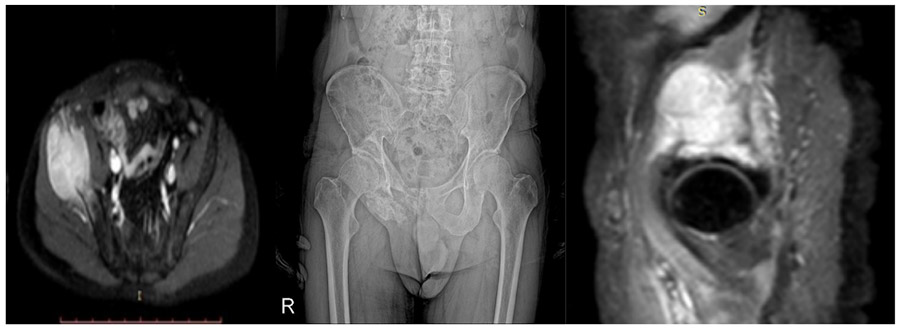

CASE 21: Risk of fracture due to metastasis of bladder cancer to the right pelvic bone (iliac wing).

Before the surgery: X-rays and MRIs show damage to the right pelvic bone and a large tumor tissue that has spread beyond the bone.